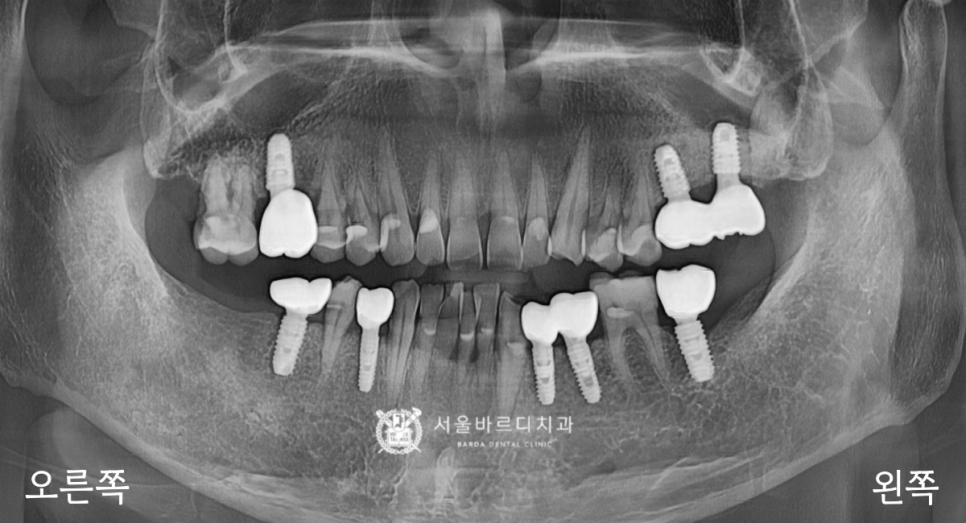

스캐너로 픽스처와 잇몸의 위치를 기록한 덕분에

맞춤 기둥을 잘 맞게 만들어 올 수 있었고,

기둥을 체결한 다음 보철을 올려서 확인해 보니

맞물림도 잘 맞아서 바로 붙여드릴 수 있었습니다.

임플란트는 뿌리가 작고, 머리가 큰 가분수 형태라서

힘을 잘 견디고, 음식을 덜 끼게 하기 위해서

두 개의 크라운을 붙여서 스플린트 형태로

만들어 드리고 있는데요.

덕분에 식사하는 힘을 더 잘 받을 수 있어서

뿌리가 찢어지거나 보철이 깨지는 등의

문제를 줄일 수 있게 되었습니다.